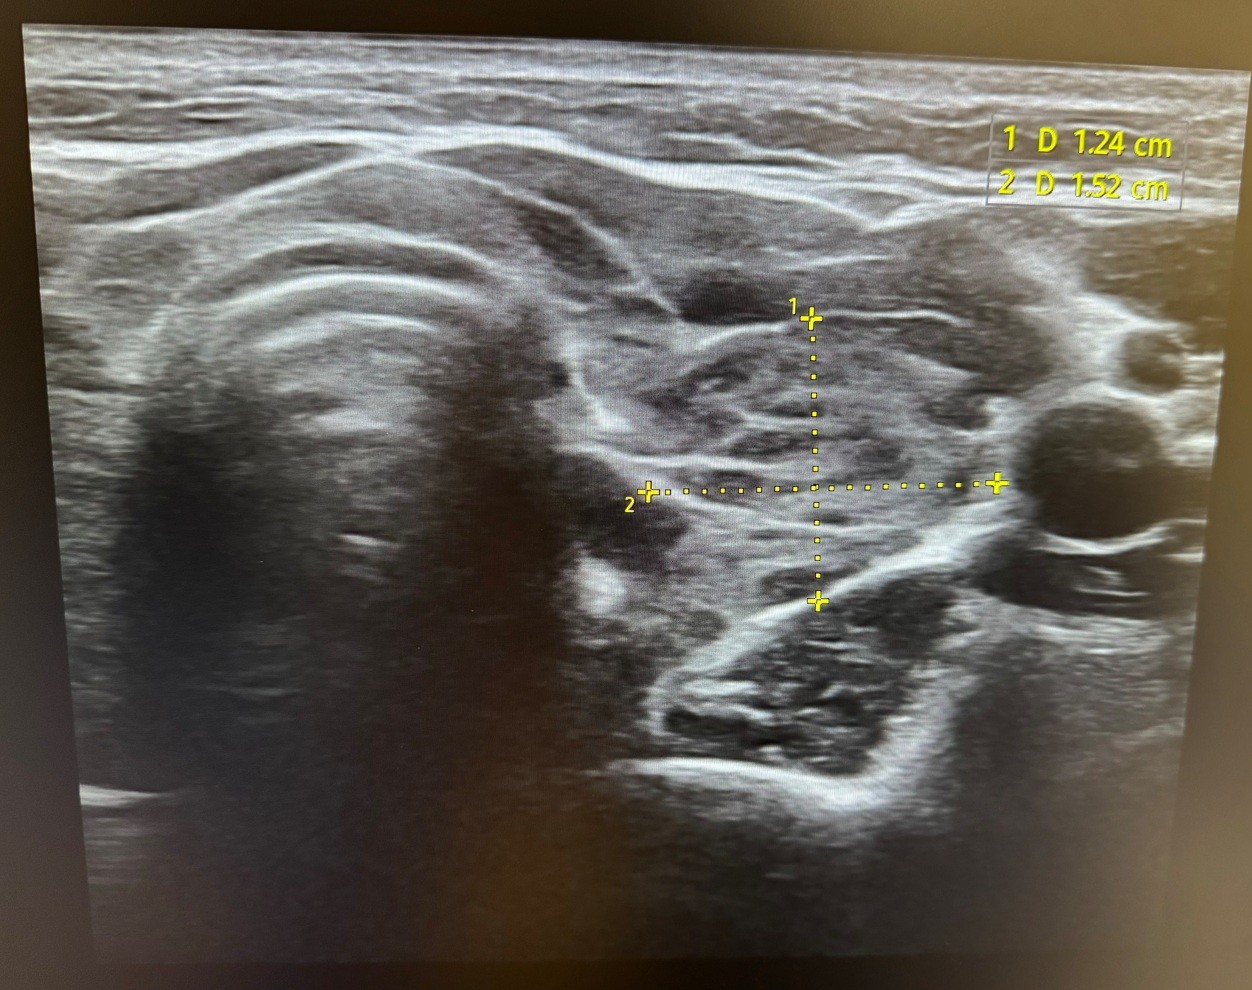

Hallazgos ecográficos

Se realiza una ecografía clínica en la que se objetiva un parénquima tiroideo de aspecto apolillado, heterogéneo con micronódulos hipoecoicos y aumento heterogéneo de la vascularización. No se identifican lesiones nodulares sospechosas de malignidad. Ambos lóbulos tiroideos e istmo presentan un tamaño dentro de la normalidad.

Estos hallazgos ecográficos, junto con la anamnesis y exploración física, orientan al diagnóstico de tiroiditis de Hashimoto.